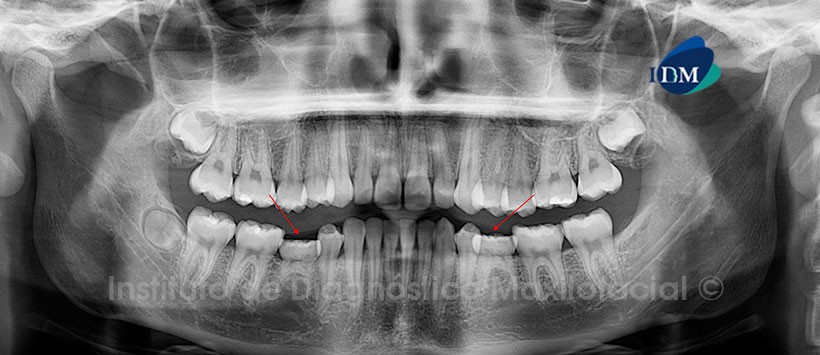

Paciente masculino de 18 años de edad que es referido para descartar las ausencias de las piezas 35 y 45; así como para la evaluación de las terceras molares. La radiografía panorámica nos muestra la persistencia de las piezas 75 y 85; las mismas que se encuentran asociadas a las ausencias de las piezas 35 y 45 respectivamente. Además, se evidencia la evolución intraósea de las piezas 18, 28 y 48; esta última se encuentra en posición bucolingual. Por otro lado se observan restauraciones coronarias a nivel de las piezas 16, 26, 46 y 47 (Fig. 1).